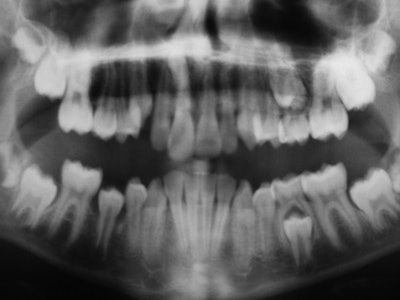

MRI yielded a clear separation between the tooth substance and the surrounding tissues, they noted. "The position and shape of malformed teeth could be assessed in all 3 spatial dimensions. The visualization software allowed viewing of the rendered structures from arbitrary angles."

Dental abnormalities were visualized from the contrast to the adjacent signal-producing dental structure, the researchers reported. "The dental pulp, bone marrow, gingival, saliva, facial soft tissues, tongue, and palate provided a signal on clinical MRI."